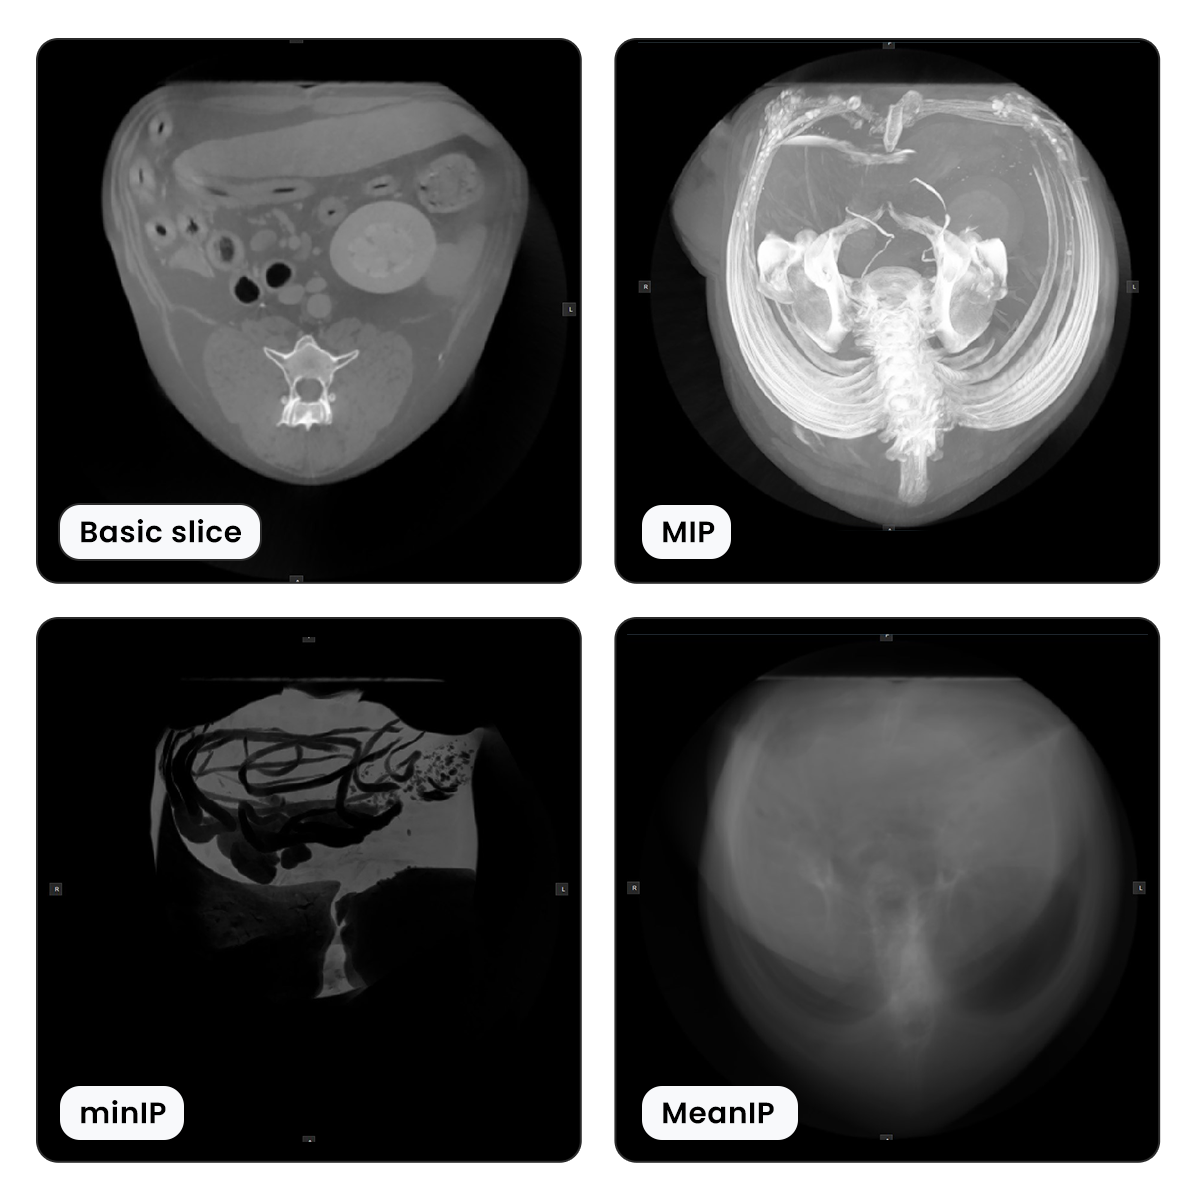

Types of Thick Slab Rendering Modes¶

There are three different thick slab rendering modes available for viewing multiple slices in one view simultaneously.

MIP - Maximum Intensity Projection: Displays the highest intensity value of each voxel from the available slices.

MinIP - Minimum Intensity Projection: Displays the lowest intensity value of each voxel from the available slices.

Mean Intensity Projection: Displays the mean average value of each voxel from the available slices.